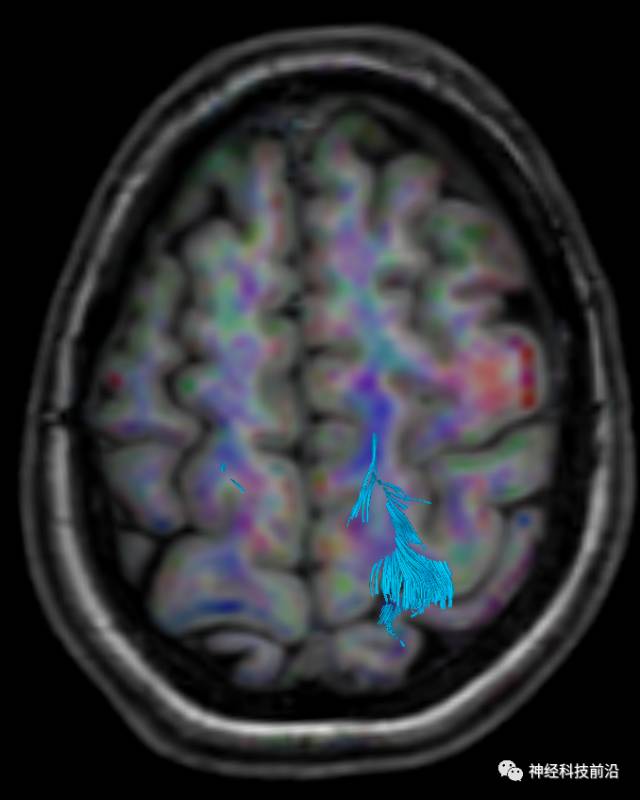

DTI原始图像与T1融合图像

皮质脊髓束与皮质脑桥束的关系毗邻